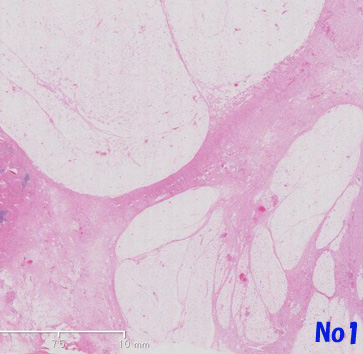

後腹膜多結節性病変は, ほとんどが成熟したように見えるfat cellから構成されている。細胞は種々のサイズ,形態を示し,小葉構造をとるmono-あるいはmultivacuolated lipoblastが散在する。線維血管性の隔壁は厚かったり薄かったりするが, その中には異型のある紡錐形あるいは多形を示す間質細胞が認められる。well differentiated lipoma様のliposarcomaの所見を呈しています。(Virtual Slide-No.1 and No.2)

no1a.jpg